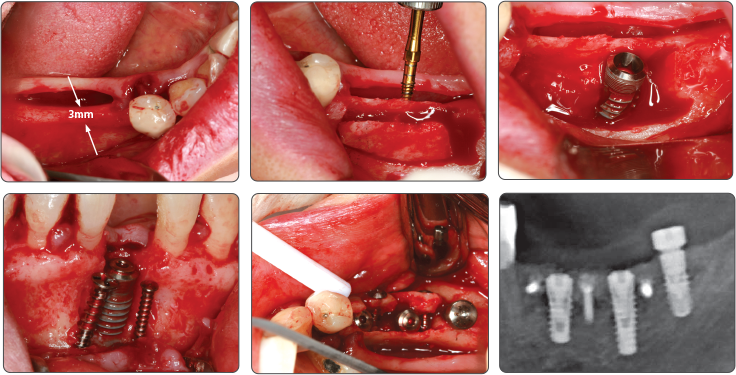

Последовательность манипуляций при синус-лифтинге

Используйте только сверло для синус-лифтинга

1. Синус-лифтинг (имплантат Ø4.0)

▶ Immediate Implantation and Sinus Lift Technique with Tap Drill (Ø4.0 Fixture)